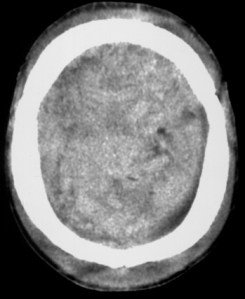

HED vertex